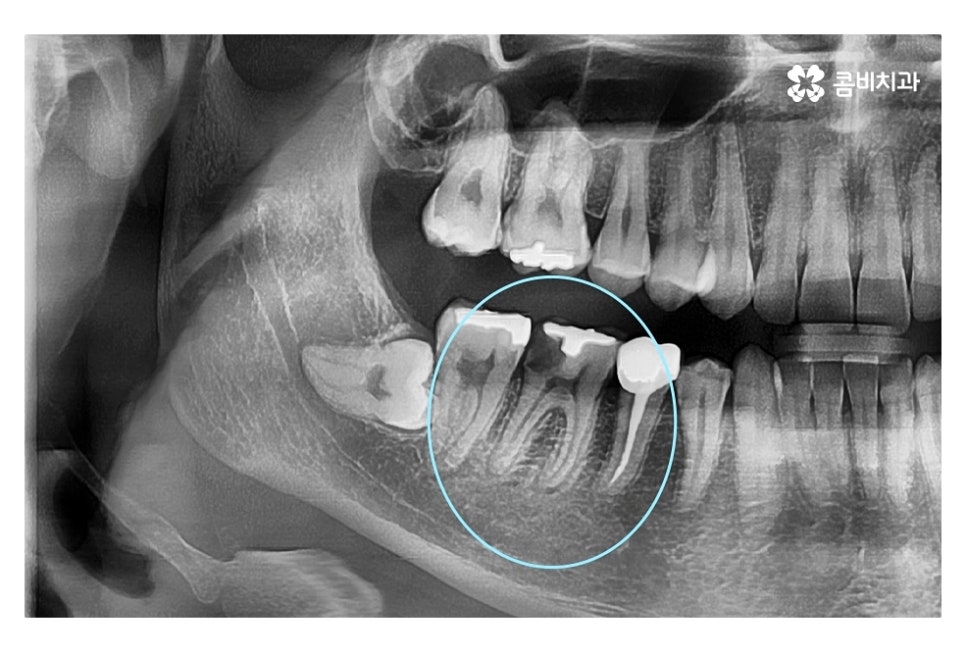

같은 환자분의 사진인데 좌측 치아의 경우 신경치료 후 크라운으로

마무리를 했지만 우측 어금니의 경우 치아의 대부분이

손상이 되어 결국 발치 후 임플란트를 하게 된 사례라고 할 수 있는데요.